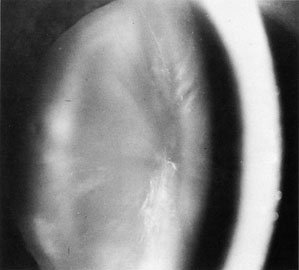

The therapeutic approach for glaucoma in these patients is the same as in traditional open-angle glaucoma. Because of the corneal findings and often concomitant cataracts, combined keratoplasty with cataract extraction frequently is needed in these eyes. The dystrophic changes in the endothelium (Fig. 8) must be estimated when glaucoma and cataract surgery are planned. If the endothelium is not severely damaged and cataract is present, it may be possible to obtain good pressure control and visual results for a long period of time with combined cataract-glaucoma procedures, when necessary.

Fig. 8. High-power photograph of endothelial dystrophy with pigment associated with open-angle glaucoma.